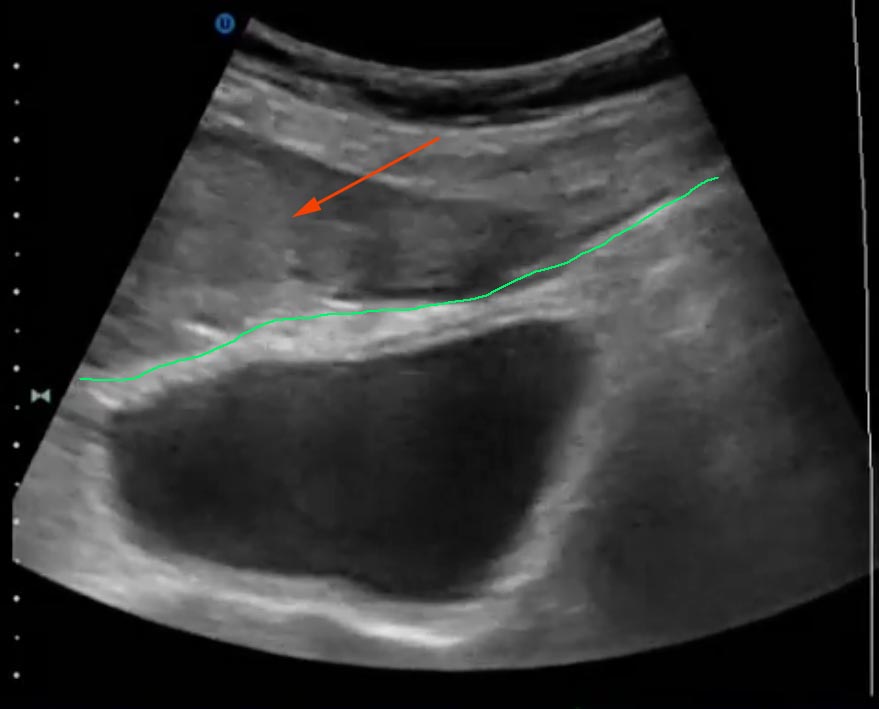

Если брюшина там где я думаю и показана зеленым, то это гематома передней брюшной стенки (сгустки - красная стрелка).

Если нет, то св. жидкость в БП (кровь скорее всего).